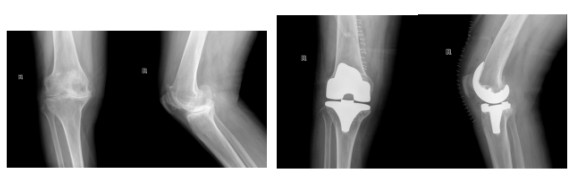

近日,阿坝州人民医院骨科成功完成我州首例“3D打印个性化定制导板辅助全膝关节置换术”,为一名饱受晚期大骨节病折磨、膝关节严重畸形的患者解除了病痛。此项技术的成功应用,标志着阿坝州在复杂骨关节疾病外科治疗领域迈入精准化、个性化“定制”新时代。

传统全膝关节置换术虽是晚期关节病变的有效手段,但对于解剖结构严重变异的大骨节病患者却存在局限。常规手术器械往往难以匹配异常骨骼,术中需反复调整截骨,导致手术时间长、出血多、术后功能恢复受限,如同“削足适履”。

本次手术的核心创新在于深度应用3D打印技术实现“个性化定制”。术前,医疗团队为患者进行高精度CT扫描,利用三维重建软件精确构建畸形膝关节的数字化模型。结合选定的膝关节假体参数,骨科医生与工程师共同设计并3D打印出完全贴合患者骨骼形态的个性化手术导板(Patient-Specific Instrumentation, PSI)。该导板在术中如同精准的“导航仪”,直接指导医生完成角度、深度和厚度均预先设定的截骨操作。

手术当日,在麻醉科、手术室团队的通力协作下,主刀医生顺利暴露患者严重畸形的膝关节。令人赞叹的是,3D打印的个性化截骨导板与患者骨骼表面实现了完美贴合。医生依据导板精准完成截骨,术前选定的关节假体被顺利植入,关节力线、屈伸间隙及软组织平衡均达到理想状态。

整台手术出血量不足200毫升,较传统方式减少近半。术后第二天,患者即在康复师指导下尝试下床站立,恢复进程顺利。患者激动地表示:“走了几十年的‘歪路’,终于能挺直腿了!”